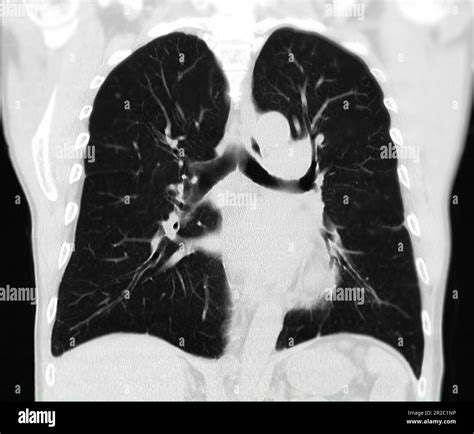

Pictures Of Lung Nodules

Lung nodules are small, round growths that appear in the lungs and can be detected through various imaging techniques, such as X-rays, CT scans, and MRI scans. These nodules can vary in size and composition, and while many are benign, some can be indicative of serious conditions, including lung cancer. Understanding pictures of lung nodules and their implications is crucial for early detection and effective treatment. This post will delve into the types of lung nodules, their causes, diagnostic methods, and the importance of early intervention.

• CT Scan: Computed tomography (CT) scans provide more detailed images and are crucial for evaluating the size, shape, and density of lung nodules.

When evaluating pictures of lung nodules, radiologists look for specific characteristics that can indicate the nature of the nodule. These characteristics include:

• Size: Larger nodules are more likely to be malignant.

• Shape: Irregular or spiculated edges are often associated with cancer.

• Density: Solid nodules are more concerning than ground-glass nodules.

• Growth Rate: Rapidly growing nodules are more likely to be malignant.